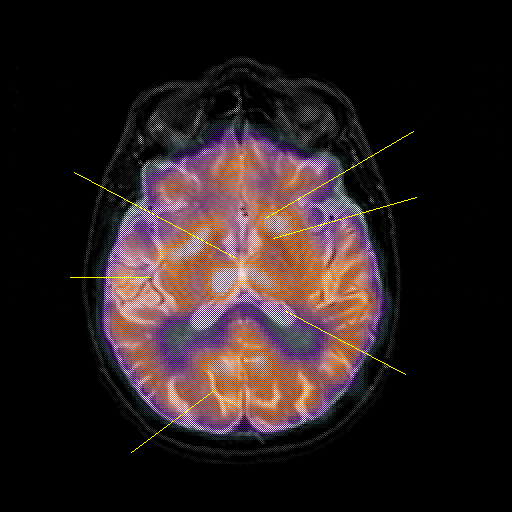

overlay : Slice 29

Slice 29

Pointers

Labeled